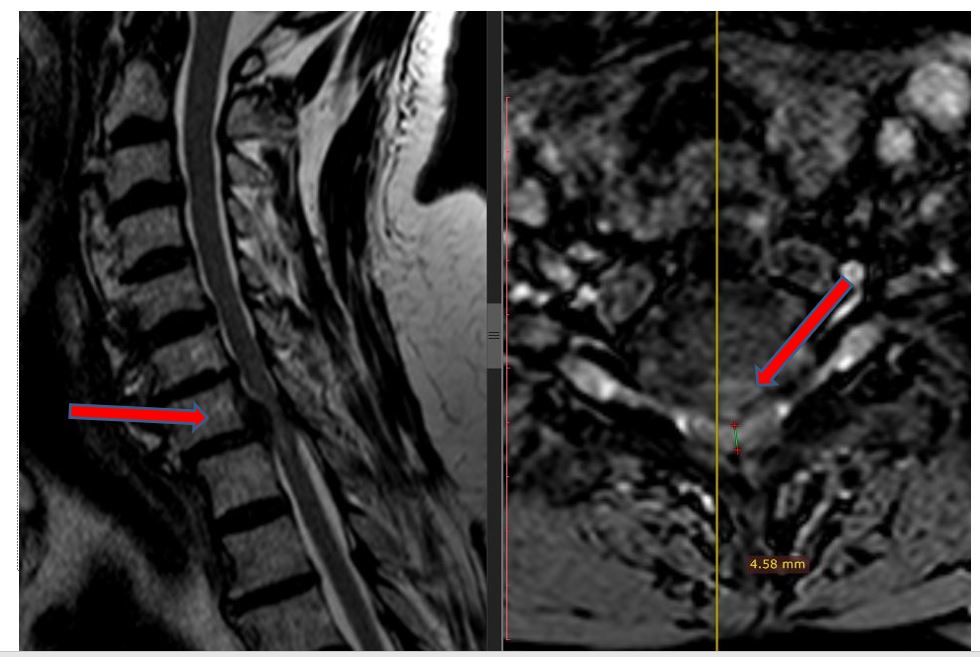

“Kur I.K erdhi te ne, veç të tjerash, kishte humbje të ekuilibrit gjatë ecjes, dhembje në të katër gjymtyrët, mpirje sidomos në këmbë (e djathta më shumë) dhe inkontinencë urinare. Rezonanca magnetike zbuloi një shtypje të fortë të palcës kurrizore në vertebrat C6-7 dhe C7-T1 të qafës. Ai gjithashtu kishte hiperostozis të segmentit cervikal të qafës gjë që i kishte bllokuar lëvizjen në të gjitha nyjet e saj. Sinjalet e shtyllës kurrizore kishin ndryshuar dhe nëse nuk do të operohej në kohë, do të ishte paralizuar plotësisht në të dyja këmbët dhe pjesërisht në të dyja duart”, tregon Prof. Dr. Kamil Cagri Kose.

Kirurgu i talentuar dhe me shumë eksperiencë tregon detajet e operacionit delikat: “Kryem korpektomi në vertebrën C7 dhe u hoq kocka e ngjeshur si dhe struktura të diskut. Gjithashtu u vendos një mbështetëse prej titani për të zgjidhur problemin dhe për të fiksuar segmentin në mënyrë që situata të mos përsëritet më”.